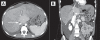

Figure 1)

Axial (A) and coronal (B) views of computed tomography angiograms demonstrating a large intrahepatic inferior vena cava thrombus (arrows)